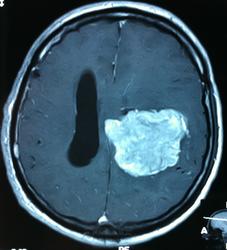

Начало вот здесь http://www.radiomed.ru/cases/kt-gms-obemnoe-obrazovanie-levoi-gemisfery-bolshogo-mozga-vnutrizheludochkovaya-meningioma. Пациент оперирован (меня сначала дезинформировали по поводу операции), перед операцией состояние ухудшилось, возникла правосторонняя гемиплегия, которая осталась и после декомпрессии. МРТ, КТ снимки и выписку предоставила супруга пациента, снимал на iphone, простите за качество, дисков с исследованиями не записывали. Надеюсь вопрос по данному случаю исчерпан.

Вот "цветочки":

T1+C

И Вы считаете, что эта опухоль имеет интравентрикулярную локализацию?

Изначально по КТ я так предпологал, а теперь на 100% уверен, разве МРТ это не показало? Гистологически - менингиома, опухоль мозговой оболочки. Покажите, пожалуйста, образование где-нибудь прилежит к костям, где есть мозговая оболочка? Я не вижу, зато отчетливо вижу в левом боковом желудочке из оболочек сосудистого сплетения. Что вас еще смущает? По-моему, предостаточно фактов, чтобы развеять все сомнения.

Пожалуйста забирайте, вот Т1 еще для полной картины.

Мне видится так. Иначе в данной локализации просто неоткуда расти оболочечной опухоли. На контрольной КТ, после декомпрессии, когда срединные структуры стали действительно срединны, правое обызвествленное сосудистое сплетение видно отчетливо, а левое, где оно? Ведь если бы образование компремировало, то после операции, когда часть мозга пролабировало в трепанационное отверстие мы бы увидели и левое сосудистое сплетение, но оно интимно связано с образованием и даже "потянулось" за ним в сторону декомпрессионного отверстия, потому что это и есть "росток" откуда выросла опухоль.